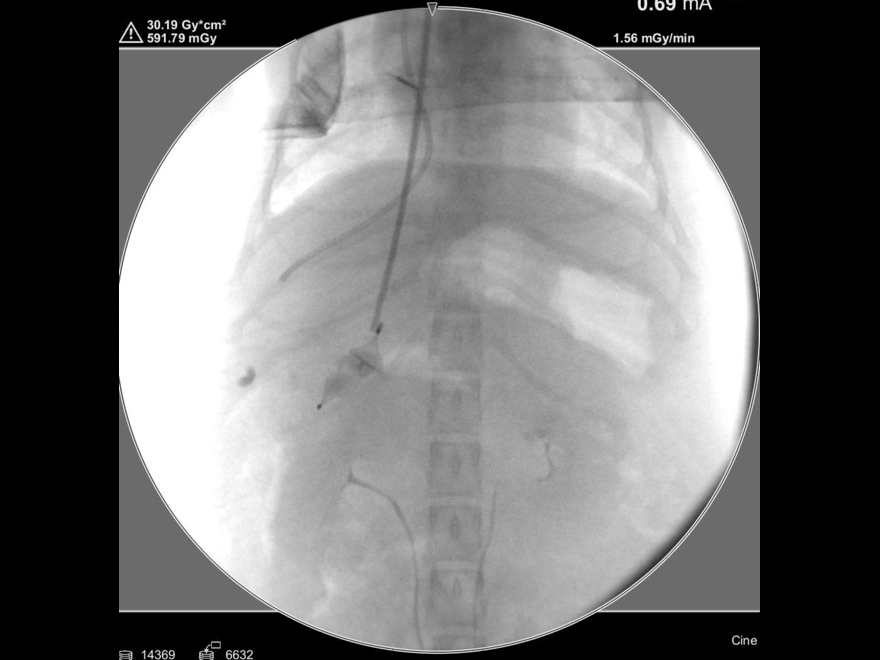

手術中の様子:セルジンガー法

手術中の様子:カテーテル設置後